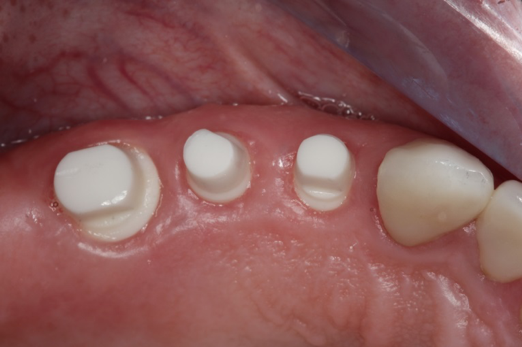

Fig 6. After splint removal (12 weeks postoperatively).

Figure 6

Fig 7. 12 weeks postoperatively.

Figure 7

Figure 3 through Figure 5 show the fitting of a one-piece multiple splint using a light-cured acrylic, along with flowable composite to adhere the splint to the three ceramic dental implants. The splint was to remain out of occlusion, without any occlusal forces for the 12-week osseointegration period. The patient was instructed to chew on the other side of her mouth for the 12 weeks before returning to the dental practice for simple removal of the splint. Removal of the splint revealed optimum results. The soft tissues were pink, with keratinized gingival margins completely surrounding the ceramic implants and consistent with what most dentists observe with the periodontium around periodontally healthy natural teeth (Figure 6 and Figure 7).